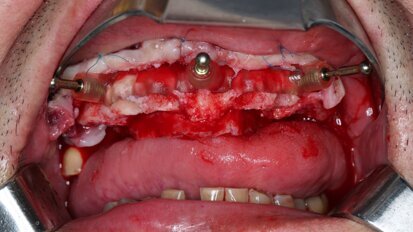

Compromised maxillary dentition treated with Straumann Pro Arch and a digital workflow

Successful immediate implant placement associated with immediate loading remains one of the greatest clinical challenges. In addition to the placement of an...